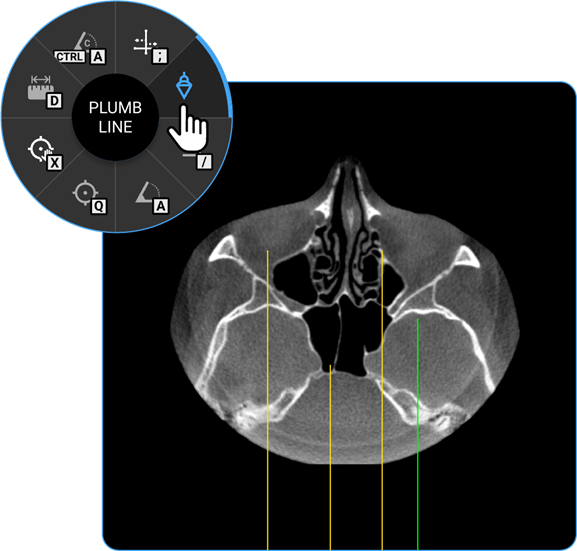

1. Plumb Line: Select the Plumb Line tool to draw a vertical reference line, helpful in assessing alignment or structural deviations.